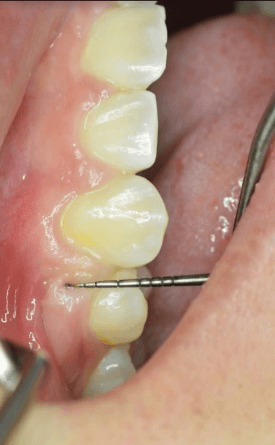

Measurements were made in the x, y, and z planes to determine gingival cleft severity. Figure 4 demonstrates a gingival cleft between the upper right second premolar and canine with the periodontal probe just outside of the cleft. Figure 5 Illustrates the same site with the periodontal probe inside the cleft in the Z direction (occlusal-gingival). Figure 6 Illustrates probing depth of the gingival cleft in the Y direction (bucco-lingual).

Figure 5: Gingival cleft with periodontal probe in Z direction.